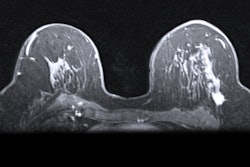

The threat of out-of-pocket costs from breast MRI may negatively affect women at greater risk of breast cancer, blocking their access to needed care, according to a study published July 28 in the Journal of the National Cancer Institute.